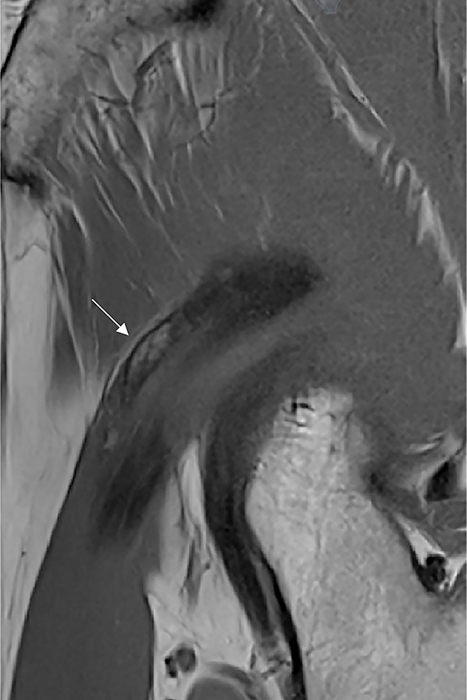

教学要点:正确诊断股直肌间接头异位骨化的线索是其位于髋臼边缘上方及其(倒置的)逗号状形态。

Teaching point: The clues to the correct diagnosis of heterotopic ossification of the indirect head of the rectus femoris are its location above the acetabular rim and its (inverted) comma‑like morphology.